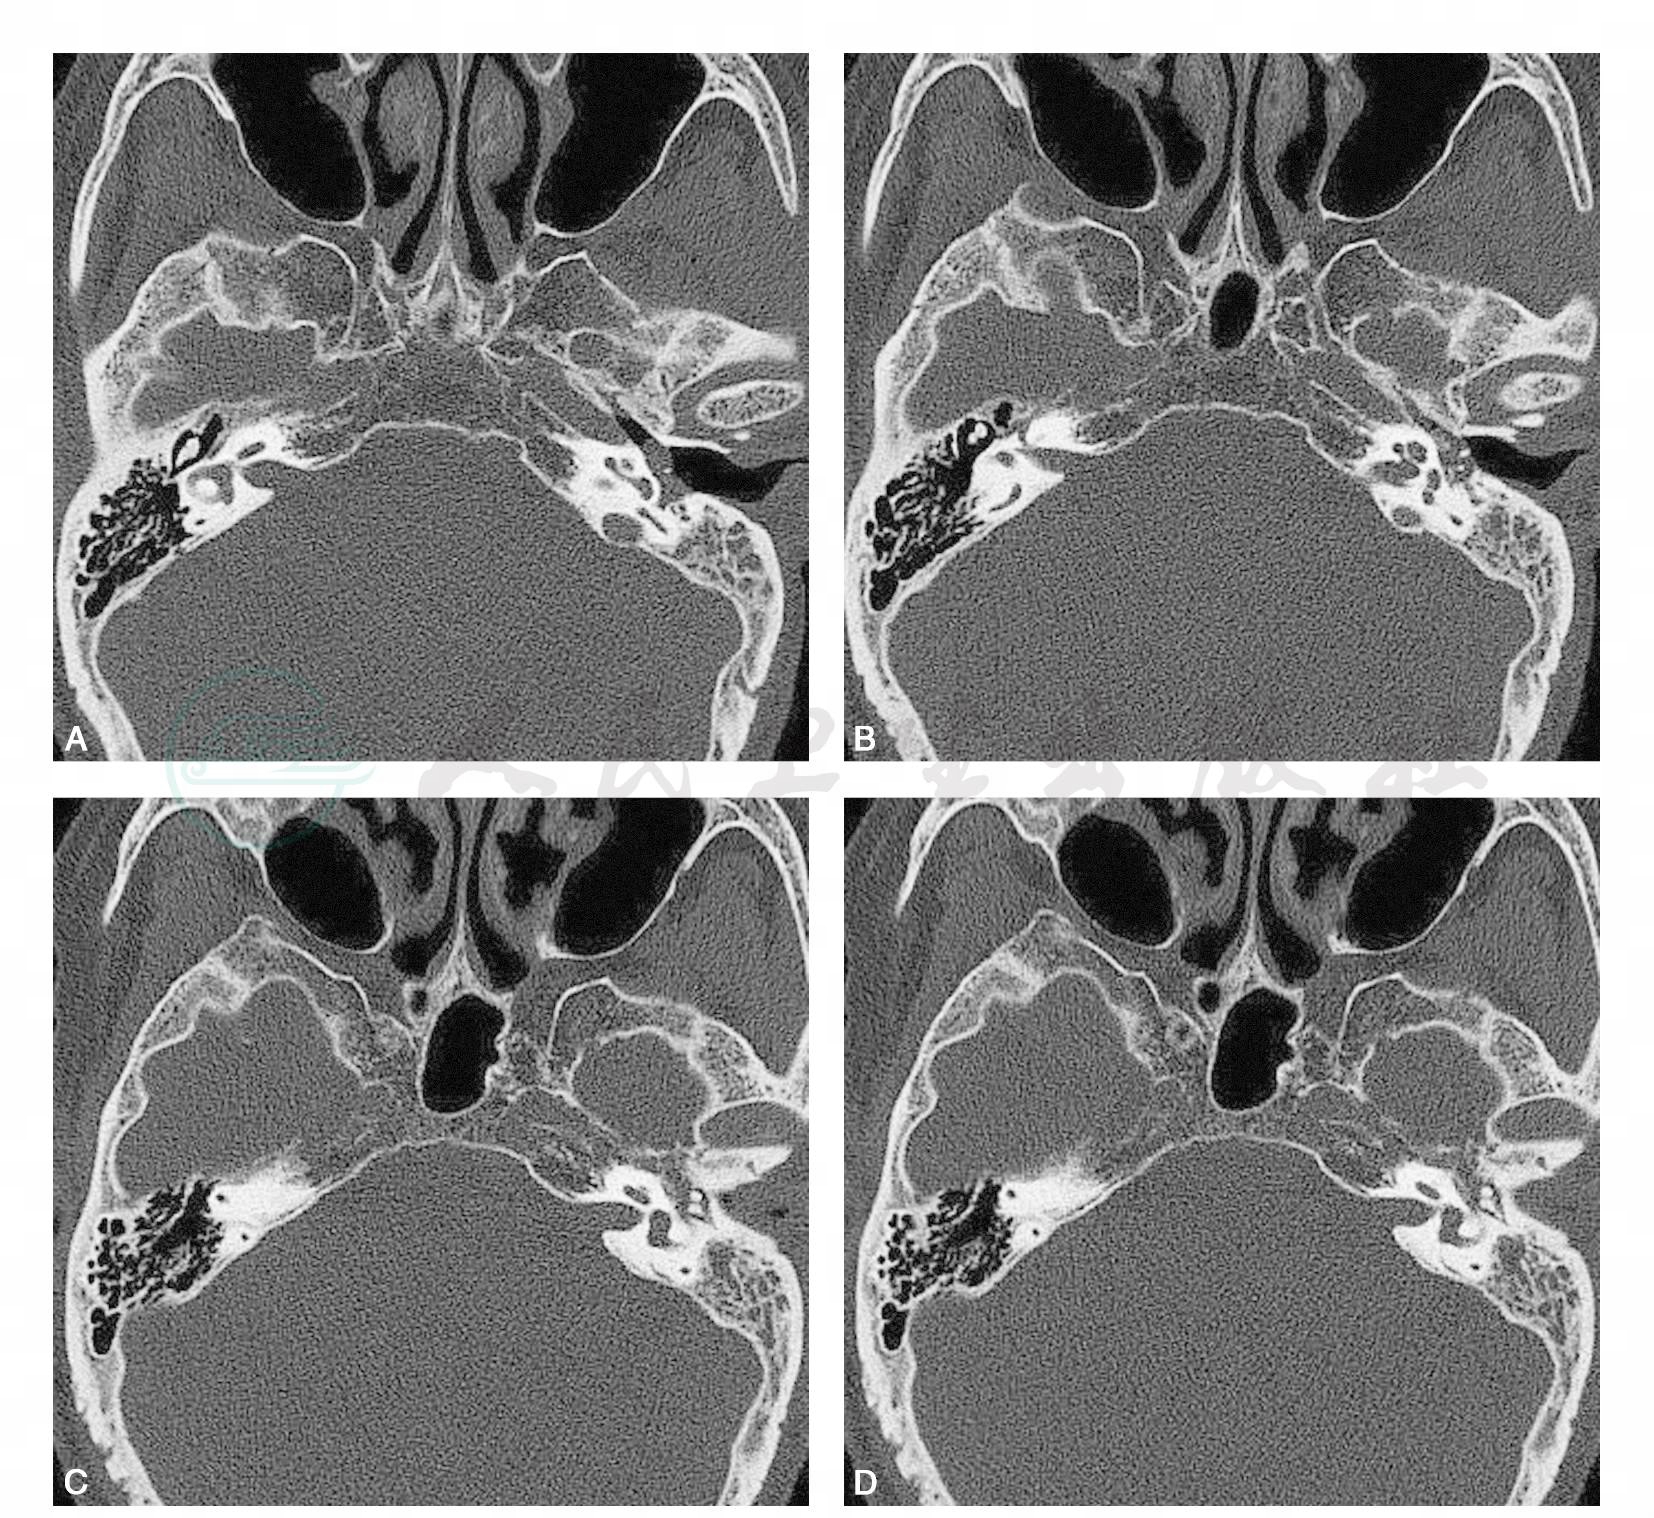

左侧鼓室内近鼓膜处见软组织样密度影,约1.0cm×0.5cm,包绕部分听小骨约相当于镫骨,内侧紧邻耳蜗,向后与颈静脉孔前壁分界清晰。影像诊断:鼓室球瘤;炎性肉芽肿(图1)。

图1 左鼓室副神经节细胞瘤

A~D.颞骨高分辨CT横断面